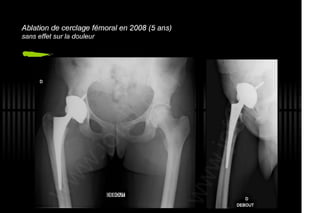

2013 032. Douleur sur PTH céramique-céramique

032. Douleur sur PTH céramique-céramique - Painfull THA with Alumine-Alumine bearing